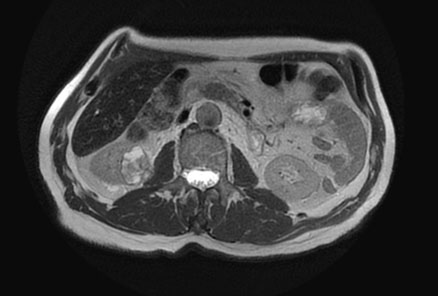

Renal magnetic resonance imaging (MRI) was performed for better characterization of the mass and showed a 3.8×2.2×3.2 cm exogenous lower pole right renal lesion with multiple thickened septations, and a soft tissue component showing heterogeneous signal on T2 images suggestive of RCC. An additional right renal pelvic mass measuring up to 2 cm in the transverse axis was found, neoplastic in nature, suggestive of TCC (Figure 1, Figure 2, Figure 3).

Figure 1: T2 sequence showing right lower pole RCC.